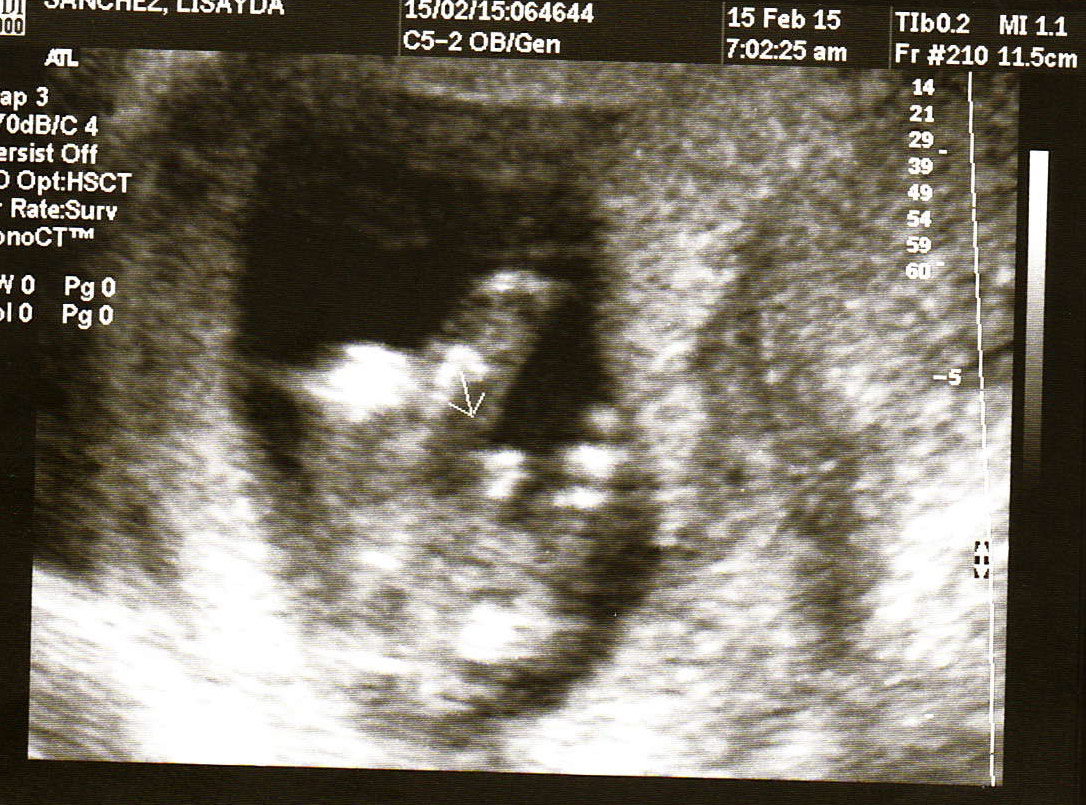

So, my wife had the ultrasound performed, we are not totally sure as to the bb's exact conception date, so we think it's between 14-16 weeks now. This is our 2nd kid. We have a boy. Looking at pictures, I can't make out what it is. I see a bulge in some, and not on others. Didn't see the 3 lines, nor did I see the turtle. What do you gals think?Attachment 27070Attachment 27069